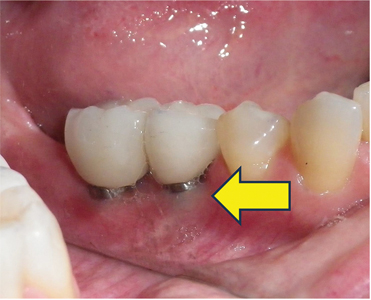

According to a study, infection and inflammation are among dental implants’ most common side effects. These are known as “peri-implants,” and they result from bacteria building up around the implant. Bacteria buildup may happen due to poor oral hygiene, improper implant placement and other pre-existing issues such as diabetes and gum disease. Also smoking and putting excessive force on the implants can also contribute to this problem. Treatment for infection may include antibiotics or deep cleaning. Surgical intervention may be required to remove the infected area and regenerate the bone if the condition is severe. Take a look at dental implant infection pictures below:

What are the dental implant infection signs to look for? The signs may include:

- The infected implant may result in redness and swelling around the implant sites

- Pus or discharge around the implant sites is a clear indication of an infection

- The loose or unstable feeling of the implant may be due to an underlying infection affecting the bone.

- Infection can also cause a low-grade fever.

According to a research, peri-implantitis can take around 5 years to progress and result in symptoms. If you notice any of these dental implant infection signs after getting a dental implant, you should promptly contact your medical professional without waiting.